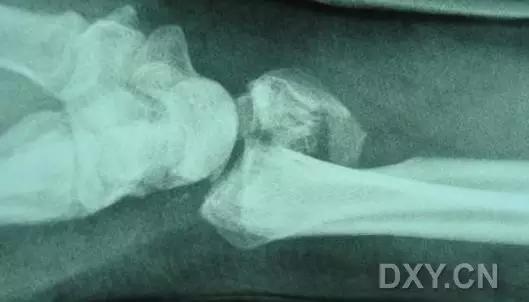

5. Hoffa 骨折

指股骨远端冠状面的骨折。

病例 1:一般股骨髁间、髁上粉碎骨折中含 Hoffa 骨折的不少见,但单纯后髁骨折则很少见。

正位片

侧位片